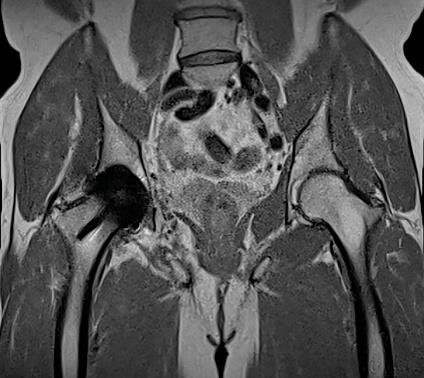

また、金属インプラントを挿入した被検者のMRI 検査も増加しているが、新しい磁場強度0.55テスラは金属アーチファクトの低減につながるため、インプラントイメージングにも有用だ。